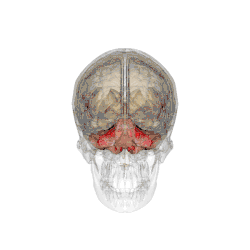

Анатомия мозжечка человека

А. Средний мозг

B. Варолиев мост

С. Продолговатый мозг

D. Спинной мозг

Е. Четвёртый желудочек

F. «древо жизни» мозжечка

G. Миндалина мозжечка

H. Передняя доля мозжечка

I. Задняя доля мозжечка

Особенностью мозжечка человека является то, что он, так же как и головной мозг, состоит из правого и левого полушарий (лат. hemispheria cerebelli) и соединяющей их непарной структуры — «червя» (лат. vermis cerebelli). Мозжечок занимает почти всю заднюю черепную ямку. Поперечник мозжечка (9-10 см) значительно больше его переднезаднего размера (3-4 см)[20].